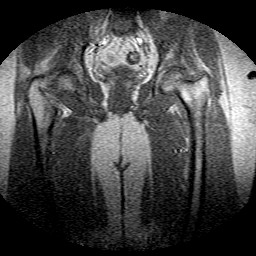

Esami: RMN BACINO

Evidenti e simmetriche alterazioni osteofitosiche in regione coxo femorale con riduzione delle rime articolari. Degenerazione completa del cercine glenoideo. Non attuali segni di versamento articolare. Non segni di edema osseo che escludono attuale algodistrofia od osteonecrosi. Lieve e simmetrica riduzione del trofismo della muscolatura glutea.